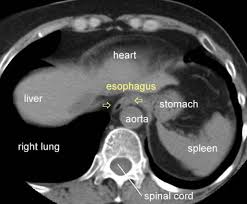

Cross sectional anatomy ct. X anatomy is a ct cross sectional human anatomy interactive medical imaging atlas for ipad iphone and ipod touch designed for medical professionals and all students of anatomy. Anatomy of the abdomen and male pelvis using cross sectional imaging ct interactive atlas of human anatomy we created an anatomical atlas of abdominal and pelvic ct which is an interactive tool for studying the conventional anatomy of the normal structures based on a multidetector computed tomography. The cross sectional plane is particularly relevant to radiology where computed tomography ct scans are primarily generated in the cross sectional axial plane.

Head and neck atlas. Cross sectional anatomy ct mri. Radiologist deciphering these photographs must be thorough in regular anatomy.

Download x anatomy click here. The cross sectional plane syn. Cross sectional imaging by modalities similar to ct and mri performs necessary function in affected person prognosis and administration.